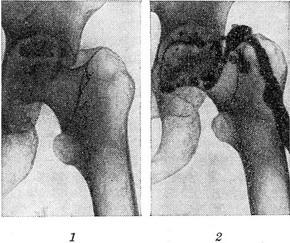

![]() Хронічний гнійний коксит, ускладнився некрозом частини головки стегнової кістки і утворенням свища: 1 - контрольна рентгенограма (до фістулографія); 2 - фистулограмма.  |

Фістулографія - методика рентгенологічного дослідження норицевих ходів шляхом заповнення їх контрастним речовиною з подальшою рентгенографією (рис.). Основним завданням фістулографія є детальне вивчення характеру та напрямки норицевих ходів і їх розгалужень, а також встановлення наявності або відсутності зв'язку між свищуватими ходами і вогнищами деструкції (зокрема в кістках) та сторонніми тілами, секвестрами, абсцесами та іншими порожнинами, розташованими в сусідніх з свищевым ходом органах. Контрастне рентгенологічне дослідження порожнини абсцесу називається абсцессографией.